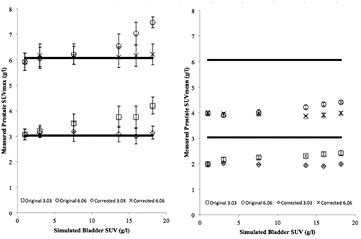

Standard image High-resolution imageFigure 5 shows the measured tumour SUVmax and SUVmean for different bladder uptakes ranging from 1.01 to 18.19 g l−1 obtained from the simulated studies with theoretical tumour SUVs of 3.03 and 6.06 g l−1. It is observed that measured tumour SUVs values were significantly increased with respect to the originally measured tumour SUV value when bladder SUV is increased. Biases of the values are shown as percentages on table 1. Measured SUVmean values underestimated the theoretical SUV in all cases, due to the small tumour size. The results were compared to the SUVmean without bladder uptake (simulated bladder uptake 1.01 g l−1) in order to evaluate repeatability. The uncertainty bars in the figure were calculated for both SUVmax and SUVmean as the standard deviation (STD) of the SUV measured for each of the five repetitions performed for each case. It can be derived from the results on figure 5 that this effect is particularly important when simulated bladder SUV is higher than theoretical tumour SUV, and that SUVmean is less sensitive to this particular effect than SUVmax. The fact that the maximum bias in the same range of bladder values is around half for a lesion with two times the simulated SUV (23.4% versus 41.3% for SUVmax and 10.8% versus 22.2% for SUVmean) is a suggestion of a strong dependency of the effect on the bladder/tumour ratio.

Figure 5. Variations on measured SUVs due to the spill-in counts from the bladder on tumours of theoretical SUVs of 3.03 and 6.06 g l−1 before the correction. SUVmax is shown on the left, and SUVmean on the right. Solid lines represent the simulated SUV on the left and the SUVmean without bladder uptake on the right.

Standard image High-resolution imageRegarding quantification, figure 8 shows the effect of the correction on quantification for lesions SUVs of 3.03 and 6.06 g l−1, showing plots of the values obtained with and without the correction. It can be observed that the error induced by the bladder has disappeared after correction. The biases induced by the bladder, shown in table 2, decreased significantly, presenting values fewer than 4% for SUVmean and fewer than 6% for SUVmax. It is observed in the uncertainty bars that the correction did not decrease the repeatability of the measurement.

Figure 8. Variation on measured SUVs due to the bladder on prostatic tumours of theoretical SUVs of 3.03 and 6.06 g l−1 before and after the correction. SUVmax is shown on the left, with SUVmean plotted on the right. The crosses represent the corrected values while the circles represent the uncorrected measurements. Solid lines represent the simulated SUV on the left and the SUVmean without bladder accumulation on the right (for graphic representation convenience). Uncertainty for each point was calculated from the statistical variations from five repetitions of the simulation.